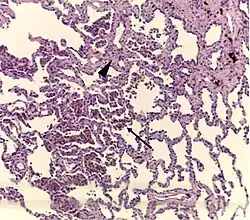

Histopathology of respiratory bronchiolitis: Smoker's macrophages (arrow); mild interstitial lymphocytic infiltrate and mild fibrosis (arrowhead)[2]